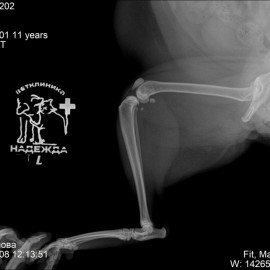

Рентгенологический снимок после проведенной операции.